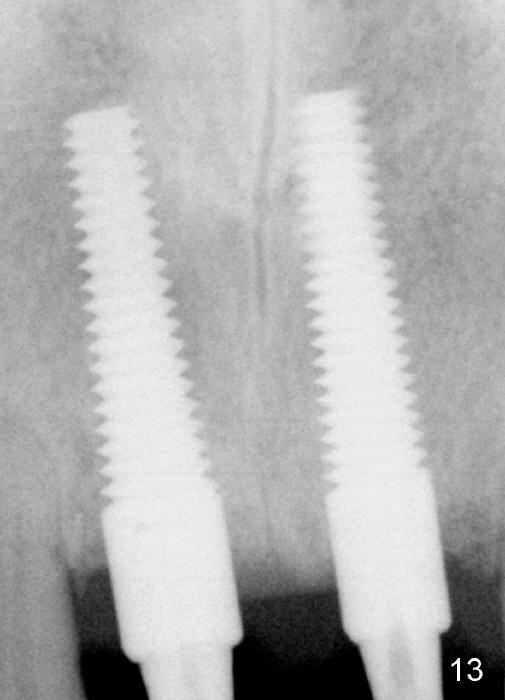

These two anterior implants remain stable 2 months 20 days postop, since one of the immediate provisionals has incisal chip (Fig.11 *) while both of them are splinted (<) to increase retention. There is no complain about paresthesia around the incisal papilla due to separation of the nasopalatine nerve. Mesiodens sockets disappear 7 months postop (Fig.13). There is no bone loss 2 years 9 months postop (Fig.14 panoramus) or 4 years 10 months postop (Fig.15,16 CT). The buccal gingiva is reddish and swollen with bleed on probing and history of pain 7 years post cementation (Fig.17). There is no bone loss in PA (Fig.18). The buccal plate at #9 is thinner than that at #8 4 years 10 months post cementation (Fig.19,20).